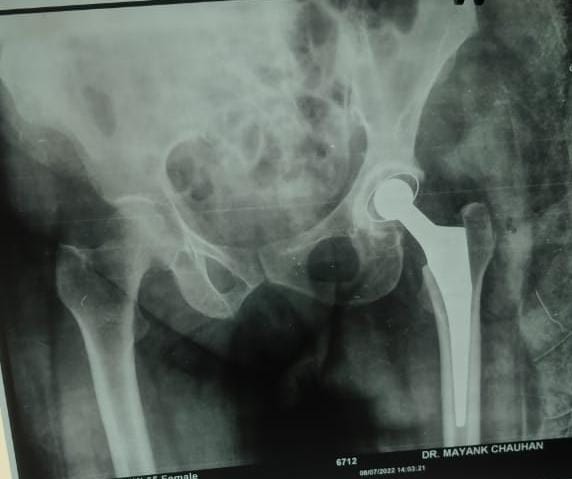

Not ready for knee replacement surgery? Dr. Mayank Chauhan, orthopedic surgeon in Noida & Greater Noida, explains 9 proven non-surgical alternatives that can delay or sometimes avoid surgery altogether.

Dr. Mayank Chauhan